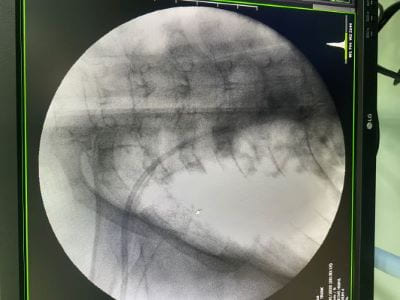

This procedure was done without fluoroscopic screening in the first 20 patients (21.5%) then used under fluoroscopic screening in the last 73 patients (78.5%) (Figure 4).